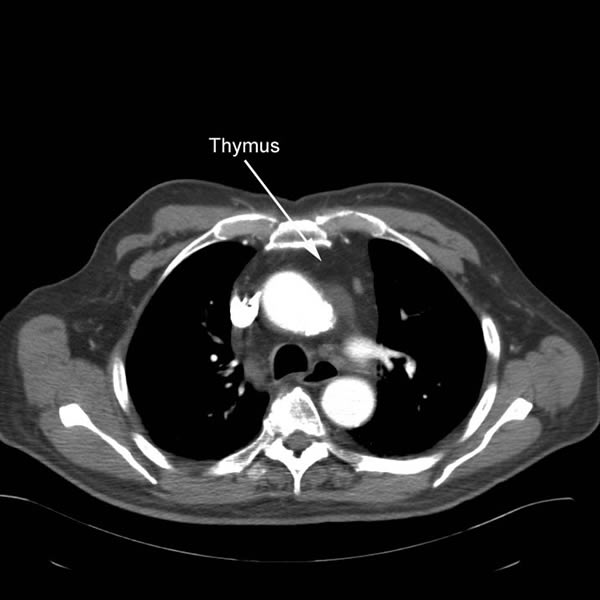

Video-assisted Extended Transcervical Thymectomy | CTSNet

Video-assisted Extended Transcervical Thymectomy | CTSNet www.ctsnet.org

thymus ct scan gland chest transcervical thymectomy assisted extended figure ctsnet thoracic pointing arrow